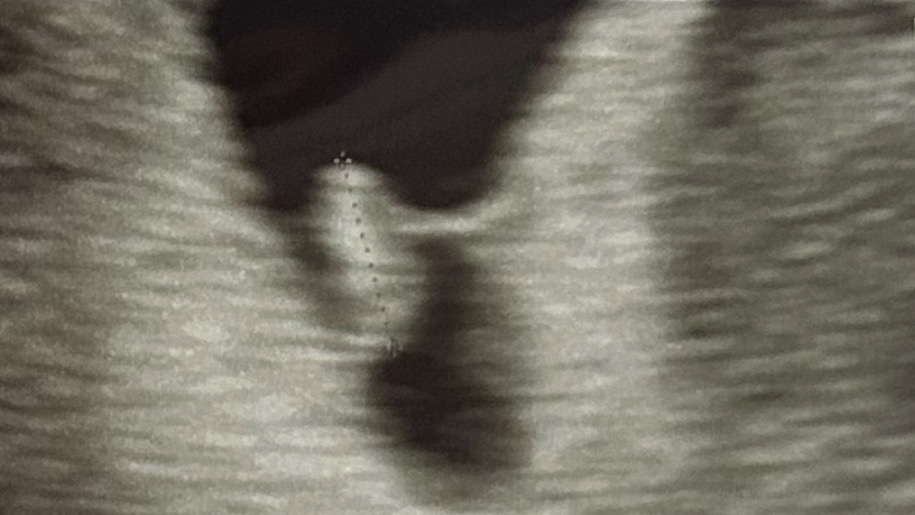

제일 처음 임신확인하고 갔을때 아기집을 봐서 아기집크기로 5주2일차였어요. 그리규 2주뒤에 오라해서 7주1일차 오늘 갔는데 난황이랑 아기랑 심장소리도 들었는데 애가 주수에 비해 6주3-4일정도라고 하네요ㅠㅠ 그리고 애가 왜이렇게 구석이 있는건지ㅠㅜ 피고임도 없고 선생님은 딱히 말씀하신건 없는데 애가 작다는 말을 들으니 조금 그렇네요ㅠㅠ 제가 생리주기도 길고 자연임신이라 그런걸까요.. 그리고 저기 연결된 선은 뭔가요..

탯줄이 아닐까요? 8주차되니 탯줄이 좀 더 선명해졌어요 저도 아기가 약간 치우쳐있었는데 당연한거래요 이때 물 많이 마시고하면서 아기집도 크기도 열심히 키워야된데용